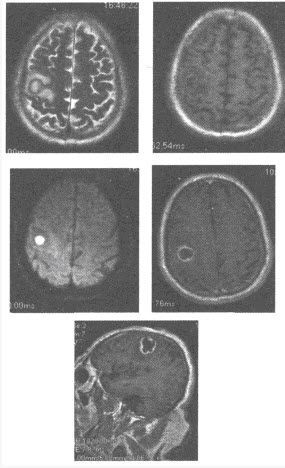

女,23岁,闭经1年余,MRI检查如图,最可能的诊断为()

A:脑膜瘤

B:表皮样囊肿

C:颅咽管瘤

D:蛛网膜囊肿

E:垂体瘤